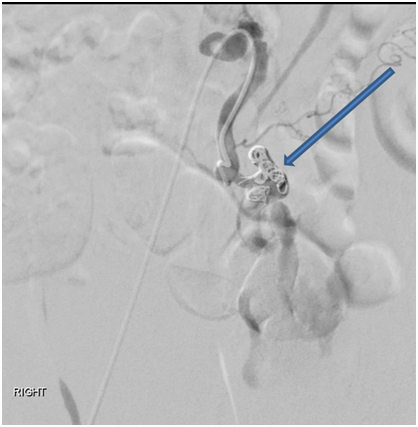

Interventional Radiology (IR) consultation was obtained and CT-guided angiography of the abdomen and pelvis was performed which demonstrated a markedly dilated, tortuous left ovarian artery with a 2.5 cm pseudo-aneurysm at the proximal to mid portion, and adjacent contrast extravasation into the retroperitoneum. At the same time, percutaneous embolization was performed using 6, 8, and 10 mm nester embolization coils as well as Gelfoam slurry (Figure 3A & 3B). Gynecologic oncology consultation was also obtained, and the decision was made not to perform a laparotomy, but to observe for further evidence of ongoing bleeding.

Figure 3B Pseudo-aneurysm was successfully embolized using 6, 8, and 10 mm nester embolization coils as well as Gelfoam slurry.